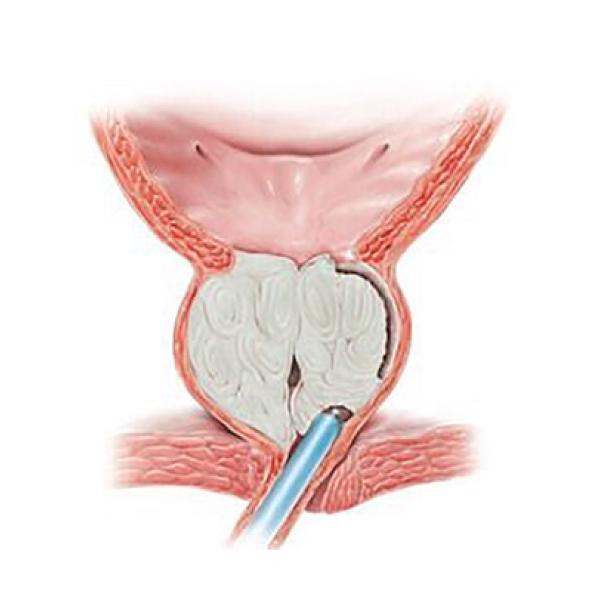

8 января пошёл на приём к урологу. Врач, произведя осмотр (крутил, вертел, сжимал пенис со всех сторон) сказал, что ничего не видит и всё c пенисом хорошо. Сказал сдать анализы и сделать ТРУЗИ предстательной железы (прикладываю фото анализов и ТРУЗИ). В итоге еще через неделю на повторном приёме, врач сказал, что было переохлаждение и как итог воспаление хронического простатита, в анализах enterococcus spp (анализы прилагаю).

Сделайте УЗИ полового члена с допплером. Если изменения не будет, то ничего не делайте, отдохните - все должно нормализоваться без лечения.